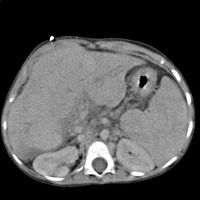

يتم استعمال اشعة الموجات الفوق صوتيةultrasonic radiology بصورة روتينية لتشخيص التليف الكبدي .يظهر الكبد المتليف في مراحله المتقدمة في هذه الاشعة بحجم صغير و عقدي وزيادة في مخطط الصدىechogenicity بالاضافة الى اماكن غير منتظمة الشكل . تستطيع الاشعة الفوق صوتية ايضا تصوير وتحري سرطانة الخلايا الكبدية hepatocellular carcinoma وفرط الضغط البابي وداء بو خياري -انسداد الوريد الكبدي Budd-Chiari syndrome

تقوم الاشعة الليفية بعمل صورة فوق صوتية للكبد -من 20 الى80ملليميتر- وقراءة ضغط -in kPa- هذه التجربة تستغرق ما بين دقيقتان ونصف الى خمس دقائق مما يجعلها اسرع من أخذ العينة بالاضافة الى انه غير مؤلم بالمرة ،هذه الاشعة تعطي نتائج منطقية لها علاقة بشدة التليف[8] هناك بعض الاشعات التشخيصية الاخرى والتي تكون مطلوبة لأسباب متخصصة مثل الأشعة التصوير المقطعي المحوسب Computerised Tomography للبطن والكبد والقناة المرارية وأيضا أشعة الرنين المغناطيسي MRI